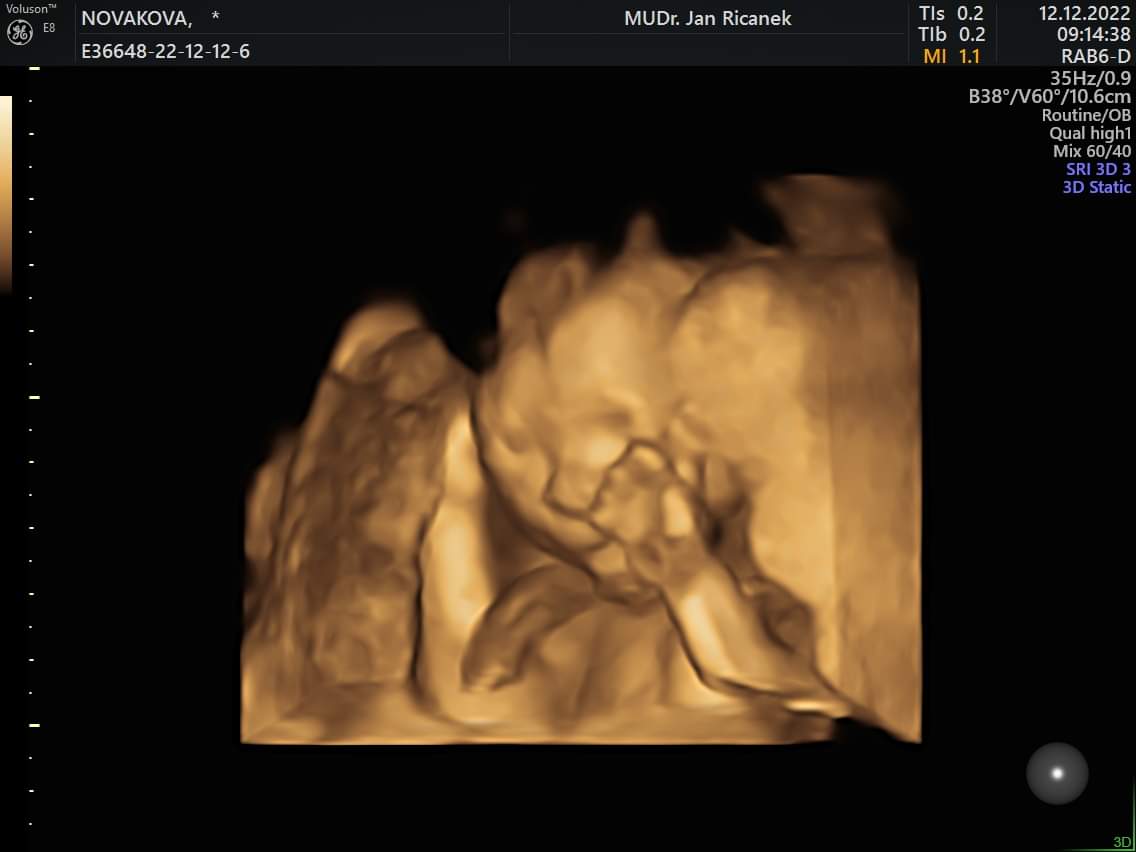

Já mám taky hezkou fotku z poslední kontroly 🤣🤣🤣 má krásnou páteř